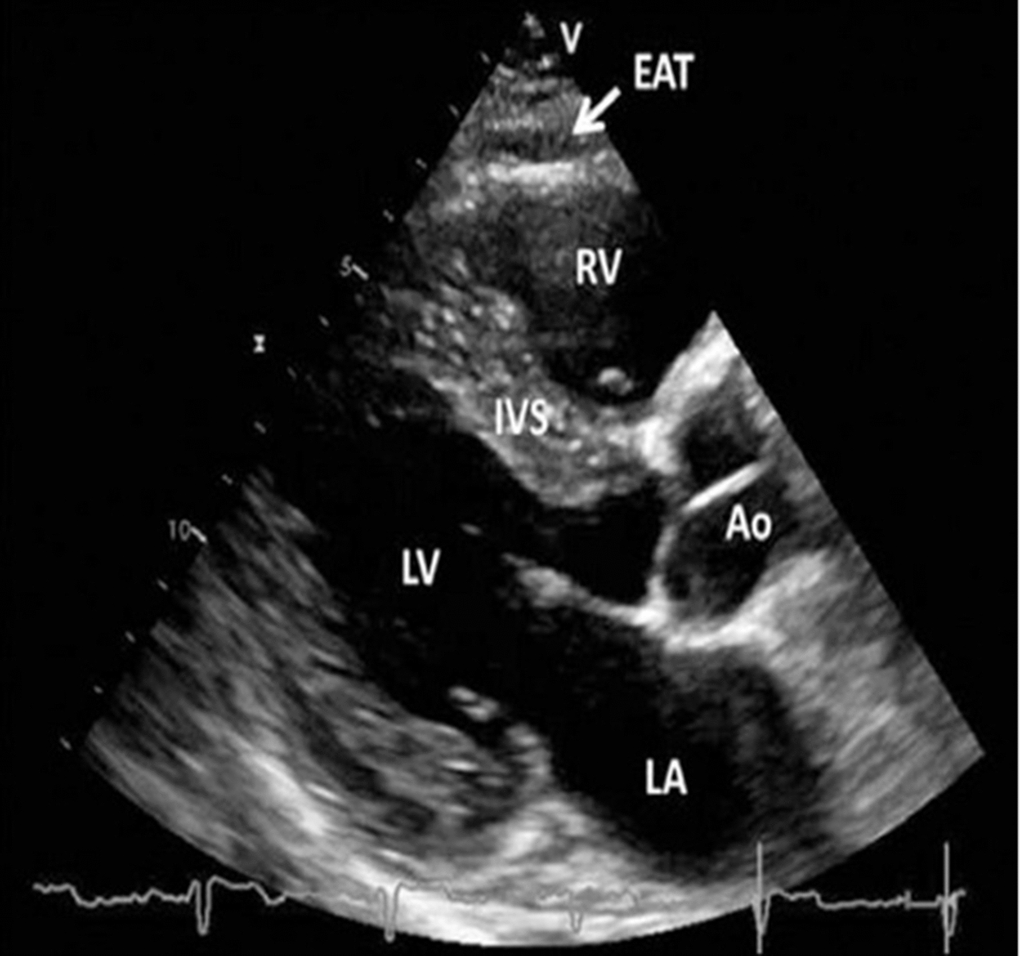

EO was evaluated by ECG in B-mode using a Vivid 5 ultrasound machine (GE, USA) with a 3.5-MHz mechanical sector sensor. The linear thickness of tEAT was measured in the parasternal position along the longitudinal axis of the left ventricle (LV) behind the free wall of the right ventricle at the end of the systole along the line maximally perpendicular to the fibrous ring of the aortic valve, which was used as an anatomical landmark (Figure 2) [36].

Figure 2. Transthoracic echocardiographic view of epicardial adipose tissue. Epicardial adipose tissue is an echo-lucent area between the epicardial surface and parietal pericardium in front of the right ventricular free wall and is indicated with a white arrow. Abbreviations: Ao, aorta; EAT, epicardial adipose tissue; IVS, interventricular septum; LA, left atrium; LV, left ventricle; RV, right ventricle [36, 37].